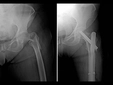

Kırık, Çıkkı ve Çatlak Nasıl Ayırt Edilir?Kırık, çıkkı ve çatlak terimleri, genellikle malzeme bilimi ve mühendislik alanında kullanılan, bir malzemenin bütünlüğü ile ilgili durumları tanımlamak için kullanılan kavramlardır. Bu terimlerin her biri, malzemenin fiziksel durumunu ve yapısal bütünlüğünü farklı şekillerde ifade eder. Bu makalede, kırık, çıkkı ve çatlak kavramları detaylı bir şekilde ele alınarak, aralarındaki farklılıklar açıklanacaktır. Kırık Nedir?Kırık, bir malzemenin veya yapının, yük veya darbe etkisiyle tamamen parçalanması durumunu ifade eder. Kırık, genellikle iki veya daha fazla parçanın ayrılmasına neden olur ve bu durum, malzemenin işlevselliğini kaybetmesine yol açar. Kırıklar, aşağıdaki gibi çeşitli şekillerde sınıflandırılabilir:

Çıkkı Nedir?Çıkkı, bir malzemenin yüzeyinde meydana gelen, ancak tam bir ayrılma durumuna yol açmayan yüzey hasarını ifade eder. Çıkkılar, genellikle yüzeyde görünür bir deformasyon oluşturur, fakat malzemenin bütünlüğü büyük ölçüde korunur. Çıkkılar, malzemenin dayanıklılığını ve performansını etkileyebilir, ancak genellikle acil bir onarım gerektirmez. Çıkkıların bazı özellikleri şunlardır:

Çatlak Nedir?Çatlak, bir malzeme içinde meydana gelen, ancak yüzeydeki bütünlüğü bozmayan bir deformasyon türüdür. Çatlaklar, genellikle malzemenin iç yapısında, stres veya gerilme sonucunda oluşur ve çeşitli boyutlarda ve şekillerde olabilir. Çatlaklar, malzemenin dayanıklılığını azaltabilir ve zamanla büyüyerek kırıklara yol açabilir. Çatlakların bazı özellikleri şunlardır:

Kırık, Çıkkı ve Çatlak Arasındaki FarklarKırık, çıkkı ve çatlak arasındaki temel farklar, bu durumların malzeme üzerindeki etkileri ve yapısal bütünlük ile ilgili farklılıklar içermektedir. Aşağıdaki tabloda bu farklar özetlenmiştir: